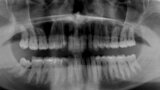

Fig. 4: Initial situation, panoramic radiograph (2015).